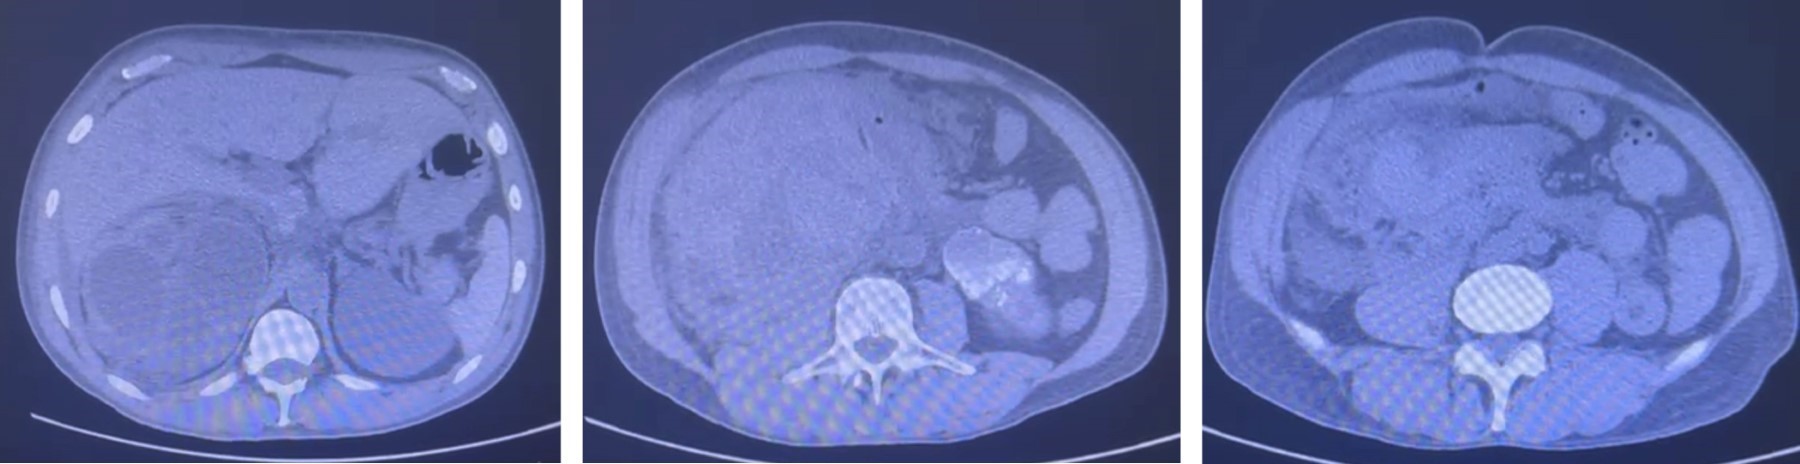

Paciente masculino de 52 años con antecedente de tuberculosis genitourinaria, actualmente inactiva con secuelas anatómicas en vías urinarias inferiores. Se presenta con dolor de inicio súbito localizado en flanco derecho, irradiado hacia fosa iliaca ipsilateral, acompañado de hematuria de aproximadamente de seis horas de inicio. A la exploración física se observa abdomen irregular por aumento de volumen en flanco e hipocondrio derechos, con hipersensibilidad a la palpación en región anteriormente mencionada. Biometría hemática (BH) con hemoglobina de 8 g/dL. Se encuentra actualmente en protocolo para trasplante renal debido a enfermedad renal terminal secundaria a las secuelas por tuberculosis. Se realiza tomografía axial computarizada (TAC) simple abdomino-pélvica, donde es evidente una colección perirrenal derecha de gran tamaño que se extiende por retroperitoneo hasta fosa iliaca ipsilateral (Figuras 1 y 2). Posteriormente, en nueva BH de control se detecta disminución de hemoglobina a 6 g/dL y datos clínicos de hipovolemia, por lo que es hemotransfundido; se realiza exploración y nefrectomía derecha concomitante debido a ruptura renal extensa. En las Figuras 3 y 4 se puede observar la pieza quirúrgica extraida. El reporte histopatológico describe pielonefritis xantogranulomatosa con tinción de Ziehl-Neelsen negativa.

Figura 1

Figura 2